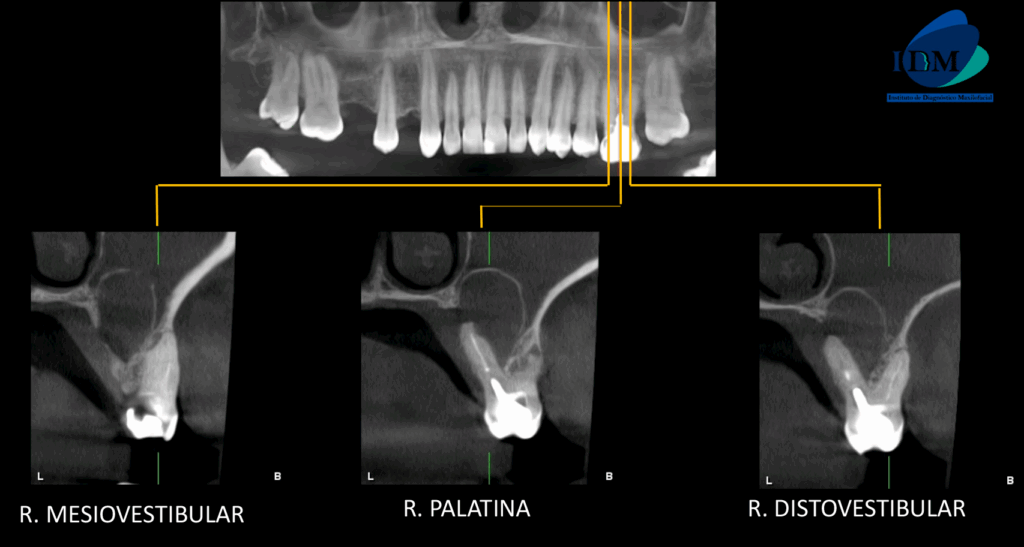

A la evaluación de la tomografía computarizada en cortes axiales, transaxiales y tangenciales se observa la pieza 16 con la raíz mesiovestibular con una obturación parcial y sobre extendida del conducto, asimismo presenta un conducto colateral obliterado y un proceso osteolítico periapical y reabsorción radicular externa del tercio apical; la raíz distovestibular presenta también una obturación parcial de conducto y la raíz palatina presenta un espigo intrarradicular, obturación parcial y subextendida del conducto y una imagen hipodensa corticalizada que desplaza hacia cefálico el piso de seno maxilar y compromete la tabla ósea palatina compatible con quiste radicular, asimismo ocasiona un engrosamiento de la mucosa antral ipsilateral compatible con sinusitis de origen odontogénico.

CORTES TRANSAXIALES